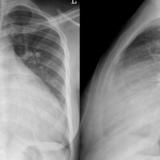

Biventricular ICD lat

Date: 10/22/2010

Views: 3205